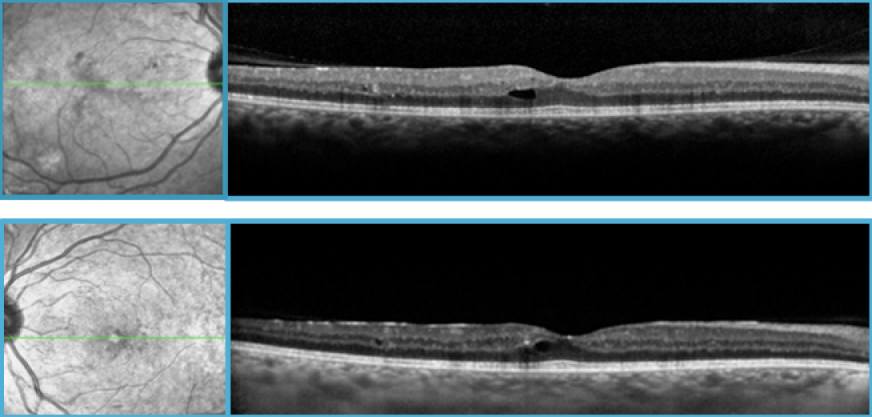

On presentation, Best Corrected Visual Acuity (BCVA) was 20/40 right eye (OD) and 20/30 left eye (OS). Slit lamp examination was normal in both eyes (OU). Fundus abnormalities included multiple microaneurysms in the posterior pole, large blot hemorrhages and venous dilation OU. Fundus fluorescein angiogram (FFA) showed large areas of capillary nonperfusion and dye leakage from preretinal neovascularisation in all quadrants OU. There was no angiographic evidence of macular ischemia or leakage. Macular spectral-domain optical coherence tomography scan (SD-OCT) showed one small intraretinal microcyst without significant macular thickening or foveal involvement OU (Figure 1 [Fig. 1]).

Figure 1: SD-OCT at presentation OU showing a small intraretinal microcyst with no significant macular thickness. No foveal involvment is shown.

Fundus examination showed extensive pan-retinal laser burns with large perimacular serous retinal detachment at the level of the temporal superior arcade as confirmed on SD-OCT (Figure 2 [Fig. 2]). FFA revealed a marked reversal of microvascular lesions and leakage. During the following days, her vision further dropped to Count Fingers (CF) due to worsening of her retinal detachment. 2 sub-conjunctival injections of 0.1 ml Betamethasone were done 24 hours apart on each eye. One month later, her BCVA improved to 20/30. SD-OCT confirmed regression of retinal detachment.

Figure 2: SD-OCT showing a large serous retinal detachment (SRD) at the level of the temporal superior arcade (arrow) OD 2 days following PRP with the PASCAL photocoagulator (A). A similar image was seen in the fellow eye (B).